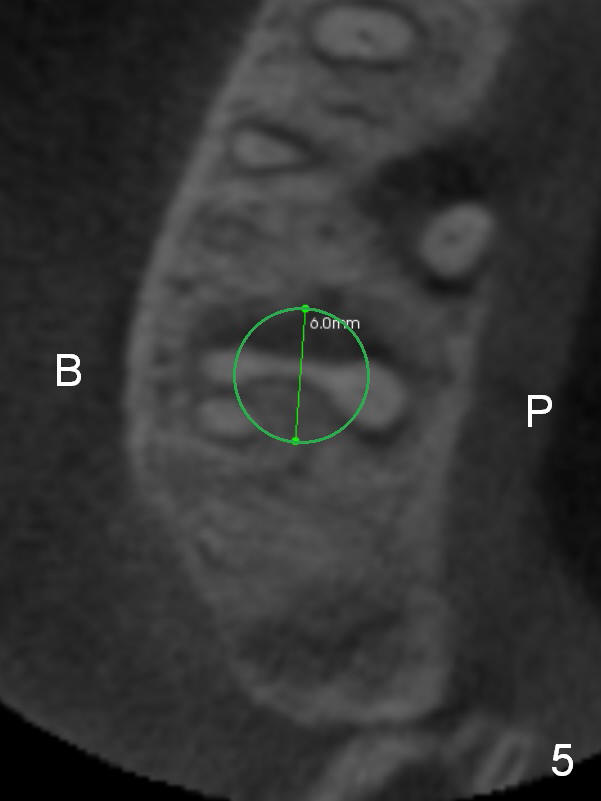

The socket is wider buccopalatally (Fig.2 (3-D disto-occlusal view),3 (coronal section)) than mesiodistally (Fig.1,4 (sagittal section),5 (axial section)). Unless more bone loss has occurred in the last year, a 6x10 mm UF implant is to be placed in the middle of the socket (Fig.6, (soaked with 2% Xylocaine/1:50,000 Epinephrine gauze)) with bone graft to be placed in the buccal and palatal gaps (red circles). Bone density in the middle of the socket is 550-700 Hounsfield units. Use RT2 or 2 mm pilot drill to start osteotomy ~ 3 mm. The largest osteotome is RT4, or largest reamer 4 mm, followed by 4.5x17 mm tap at 14 mm, until 6x17 mm one. Make sure that the sinus floor is penetrated.